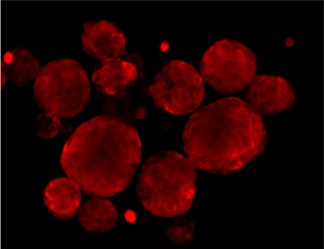

Immunofluorescence staining of Src and Phospho-Src

SRC total

P-SRC Tyr416